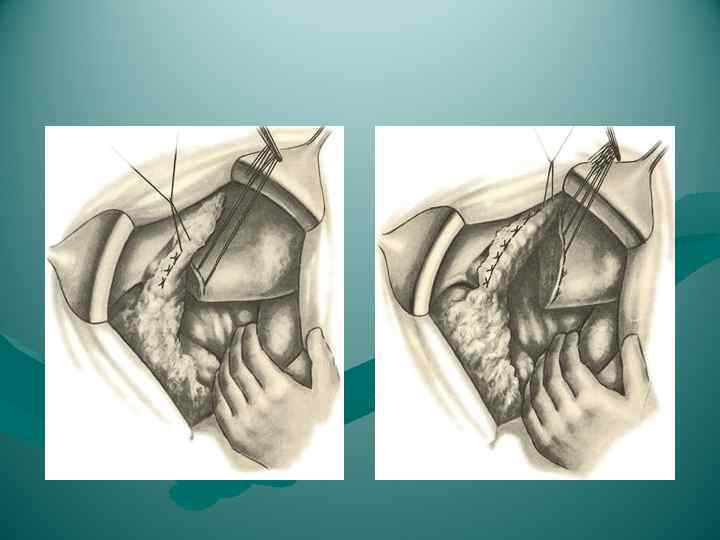

Мобилизация левой доли

Мобилизация левой доли

Мобилизация правой доли

Мобилизация правой доли

ПЕРЕВЯЗКА ОБРАЗОВАНИЙ В ВОРОТАХ ЛЕВОЙ ДОЛИ ПЕЧЕНИ

ПЕРЕВЯЗКА ОБРАЗОВАНИЙ В ВОРОТАХ ЛЕВОЙ ДОЛИ ПЕЧЕНИ